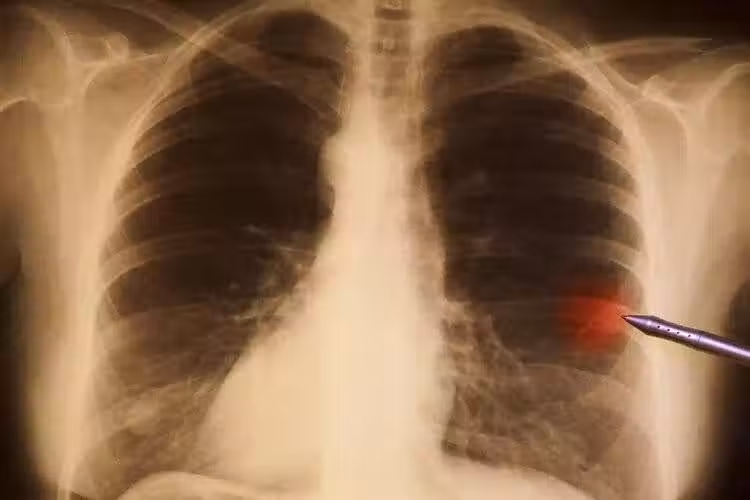

4、胃癌

作為我國的第二大癌症,胃癌的發病數和死亡數不容樂觀。數據顯示,2018年我國每年胃癌新發67.9萬例,死亡49.8萬,約佔全球的50%,其中約90%的患者在確診時已是晚期。

胃癌晚期,意味著治療費用更高、治療效果更差、5年生存率更低,給個人和家庭帶來沉重的負擔。

想要提升胃癌的生存率,就要及時抓住癥狀,比如:上腹不適,尤其是餐後腹部飽脹、胸後部疼痛、胃部反流等;大便呈柏油色、黑色;短時間內體重大幅度下降。這些癥狀可能與胃癌有關,應及時檢查。